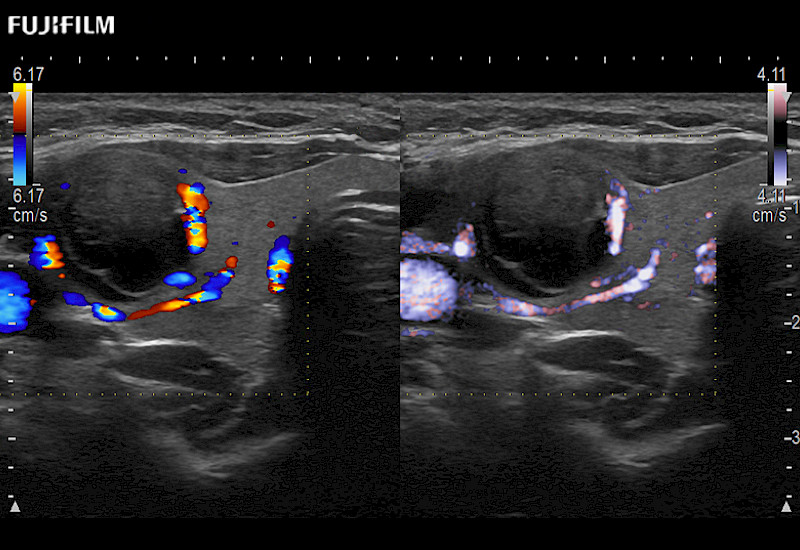

The ARIETTA 750 incorporates all of the proven technologies and functions that medical professionals have come to expect from Fujifilm Healthcare.

ARIETTA 750 is the definitive diagnostic ultrasound solution for any clinical setting - Private Office, Imaging Center, or Hospital. The ARIETTA platform provides the ultimate in clinical performance with its state-of-the-art features and large user-friendly display.

The ARIETTA 650 DI combines trusted Fujifilm Healthcare technologies and features tailored for surgical oncology.

Designed to meet the demands of surgeons, the ARIETTA 650 DI offers precise guidance. Its advanced capabilities and large, intuitive display offer accurate and efficient care in operating rooms and specialized surgical settings.